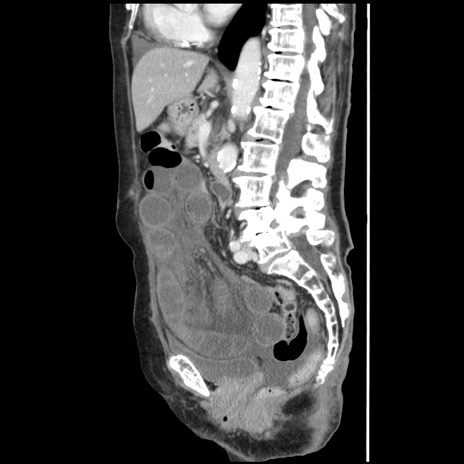

症例1(矢状断像)

【症例】80歳代女性

【主訴】腹痛

【現病歴】8時間前から腹痛あり来院。

【既往歴】糖尿病、脂質異常症、子宮体癌にて子宮全摘術

【身体所見】意識清明・会話良好だが腹痛で苦悶様、全腹部にわたって反跳痛と圧痛あり

【データ】WBC 13600、CRP 0.14、LDH 224、CK 90